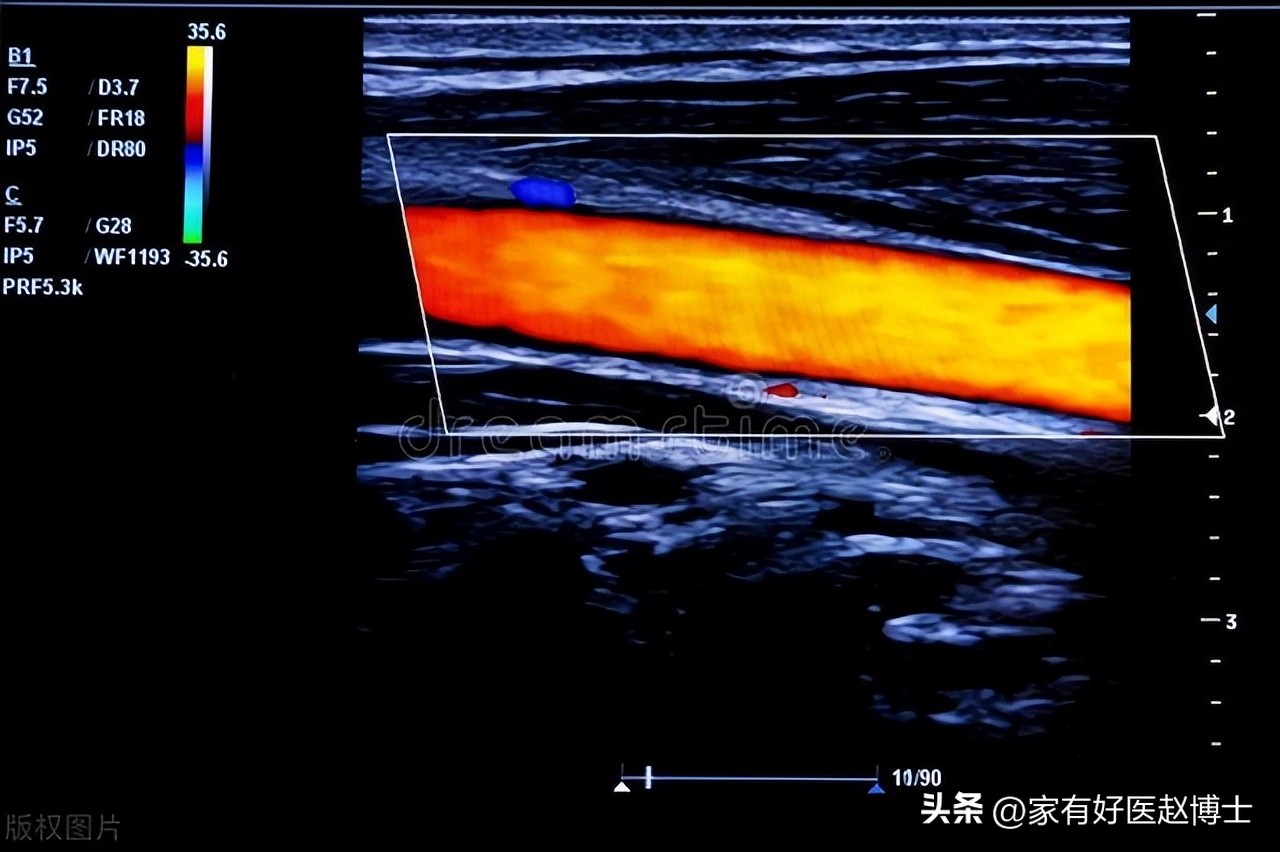

医学研究表明,当斑块在超声上表现出某些特定征象时,往往提示稳定性较差、容易发生破溃从而引起心血管事件,而这样的一些征象就被命名为“高危斑块特征”。

比较典型的“高危斑块特征”有以下这些:

第一,溃疡型斑块。 这主要是指斑块的“表面”不光滑、不平整,有类似“溃疡”的表现;

第二,无回声/低回声斑块。 这里所说的“无回声”或者“低回声”斑块,不仅包括以无回声或低回声为主的斑块;同时,也包括存在部分无回声或低回声区域的“混杂/混合回声”斑块。简单来说,只有内部回声均匀且以“等回声”或“强回声”为主的斑块,才属于相对比较稳定的斑块;而除此以外的“低回声”、“无回声”以及“混杂回声”斑块,则多属于相对不稳定的高危斑块;

第三,管腔旁暗区面积较大。 具体来说,有研究提出:如果超声报告提示颈动脉管腔旁的暗区(低回声)面积>10mm²,那么,后期发生脑卒中的风险会明显增加;

第四,斑块内有明显的新生血管;

第五,斑块内存在出血迹象;

第六,斑块表面有“微栓子”形成的迹象等等。